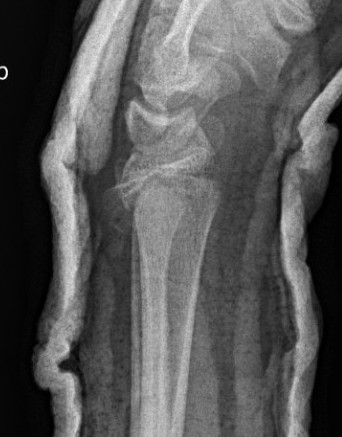

Physeal distal radius fracture

Physeal injuries

- risk growth plate arrest

- consider leaving < 50% displacement

- single reduction attempt only